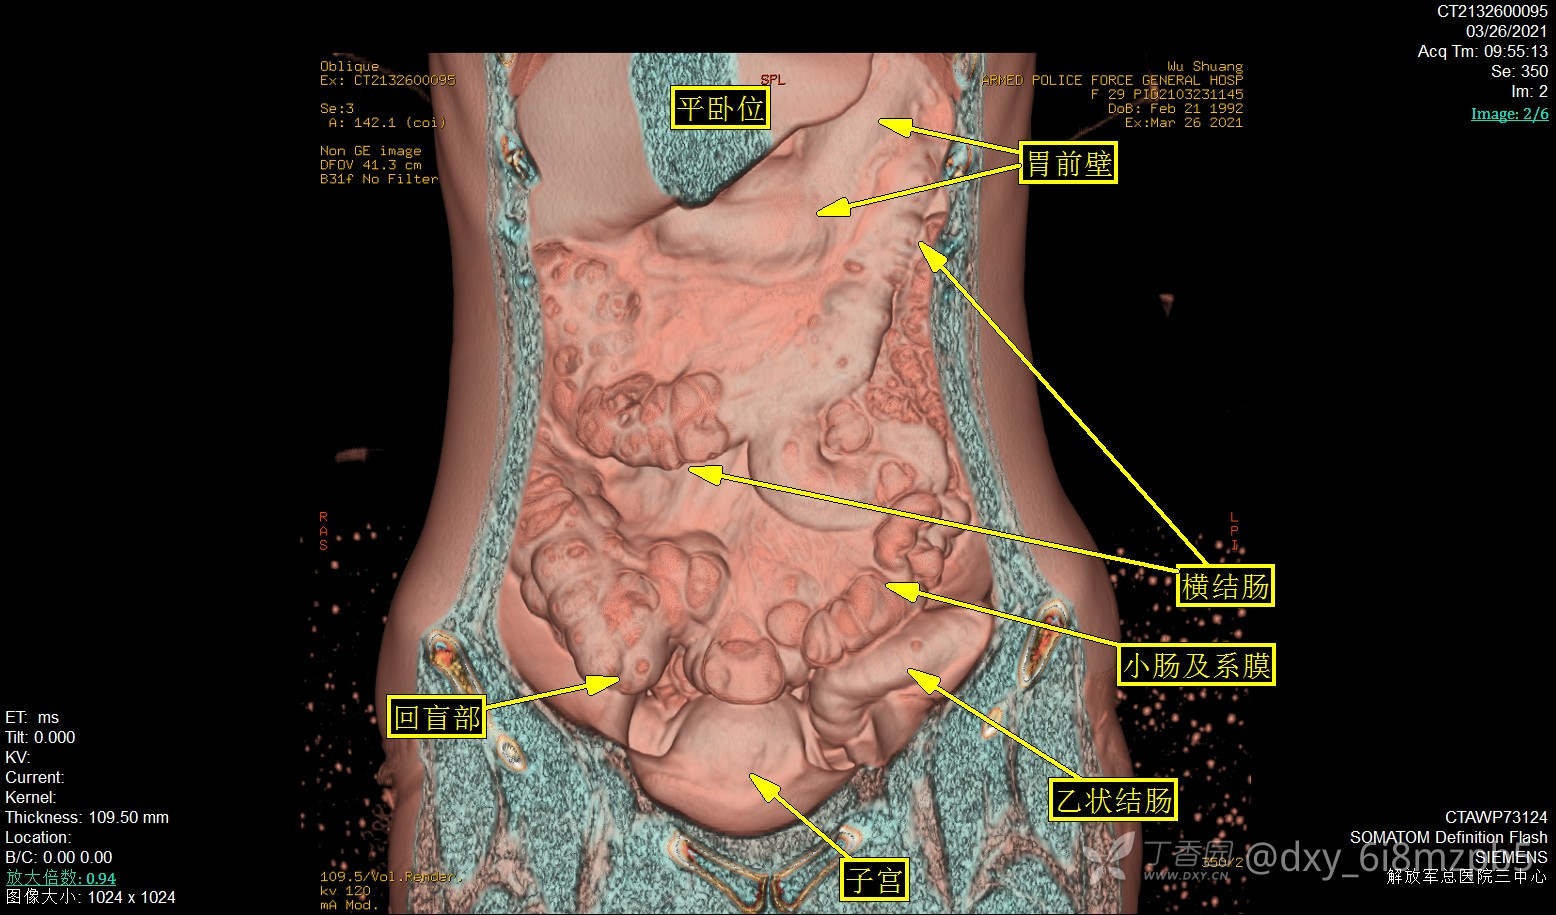

2021-3-26平卧位,左下腹18#套管针穿刺,腹腔注气2000ml,人工气腹后腹部多体位平扫,GE图像工作站进行数据VR成像(腹膜腔三维成像):

平卧位:腹膜腔气腹空间完整,肝脾形态位置正常,结肠小肠肠管平面分布,管径大致形态正常。结肠内容物偏多,48小时口服显影线位于横结肠左半以远。子宫形态大小正常。

气腹平卧位图:上腹部见肝脏、胃远端大部、横结肠正常形态。回盲部及升结肠充盈,相连回肠襻形态大致正常。盆腔见正中位子宫前壁。左下腹见乙状结肠。

平卧位图:中下腹肠管平铺,未见腹壁粘连。

左侧卧位图:显示更多右半结肠形态细节,见回盲部阑尾,末端回肠近乎正常形态。